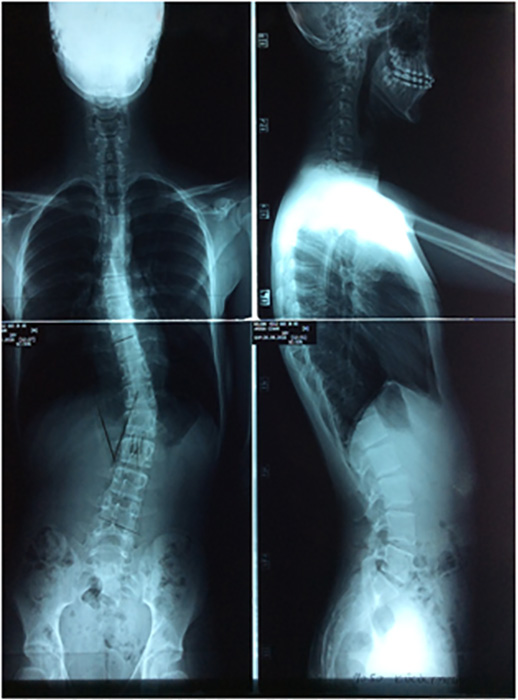

Başın bir tarafa doğru eğimli olması, göğüs kafesinde asimetri, kürek kemiklerinden birinin diğerine göre daha tümsek şeklinde olması, kalçalar ve omuz seviyeleri eşit olmaması, bacak eşitliklerinin aynı olmadığından şikayet edilmesi gibi durumlar skolyoz habercisi olabileceğinin beliren Prof. Dr. Bahadır, “Skolyozun ilerleyişi kişinin yaşı, cinsiyeti, eğriliğin tipi ve büyüklüğüyle farklılık gösterir. Skolyoz kız çocuklarında daha fazla görülmektedir. Hızlı büyümenin olduğu ergenlikte eğrilik hızlı ilerler. Skolyozun tanısı için dikkatli bir muayene ve basit bir röntgen filmi yeterlidir. Yalnız her eğrilik skolyoz değildir. Skolyozda vertebra eğimi 10 derecenin üzerinde olmaldır. Bunun altındaki eğrilikler skolyoz olarak sınıflandırılmaz” şeklinde konuştu.